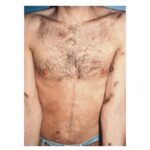

AIDS KS differs from classic KS by its more rapid course and its rapid multifocal dissemination: early AIDS-KS lesions appear as small oval violaceous macules that develop rapidly into plaques and small nodules. They are frequently present at multiple locations at

disease onset and have a tendency for rapid progression. In contrast to other variants of KS, the initial lesions in AIDS patients frequently develop on the face, especially on the nose, eyelids, and ears, and on the trunk, where the lesions follow the relaxed skin tension lines . If untreated, disseminated AIDS-KS lesions may coalesce to form large plaques involving large areas of the face, the trunk, or extremities and lead to functional impairments. The oral mucosa is frequently involved and represents the presenting site in 10 percent to 15 percent of AIDS KS . Involvement of the pharynx is not uncommon and may result in difficulty eating, speaking, and breathing.